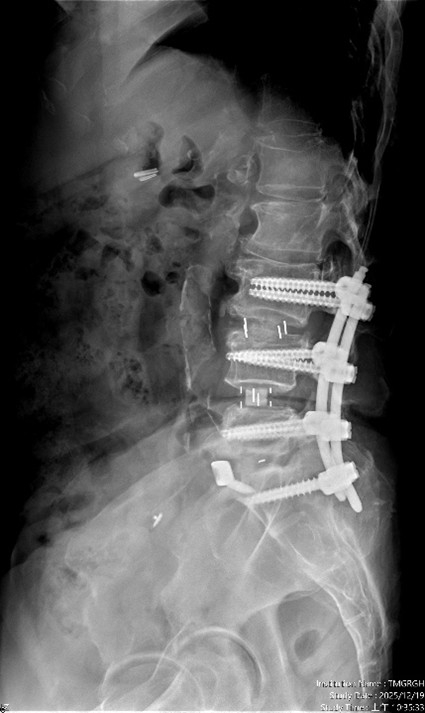

【記者張原銘、張皓傑台中報導】65歲婦人,長期飽受腰痛、下肢痠麻及坐骨神經痛所苦,行走距離逐年縮短,嚴重影響日常生活。過去曾接受膝關節保膝手術及脊椎內視鏡減壓治療,初期恢復良好,惟因仍存在多節段腰椎退化性狹窄與骨刺問題,加上彎腰負重及久坐等生活習慣未能完全改善,症狀逐漸惡化,甚至出現神經性跛行。經臺中市立老人復健綜合醫院骨科部副部長林琮凱醫師詳細檢查後,診斷為第三、四、五腰椎合併第一薦椎之多節段脊椎狹窄與神經壓迫。醫療團隊與病患及家屬充分溝通後,決定採用電腦導航輔助之前位/前側位脊椎融合手術,並合併後方骨釘固定,一次完成多節段重建。術後病患神經症狀明顯改善,行走能力恢復,生活品質大幅提升。

相較於傳統脊椎手術需分部位、分階段進行,且住院與復原時間較長,中醫大市醫引進的前位或前側位脊椎融合手術,搭配3D電腦導航系統,可於同一次手術中完成多節段融合與多部位重建。手術採「間接減壓」方式,不需直接進入脊椎腔,大幅降低神經損傷風險。多數病患可於手術當日或隔日,在配戴背架下即可下床行走,術後疼痛較少、恢復期明顯縮短,同時提升醫療效能與病患滿意度。